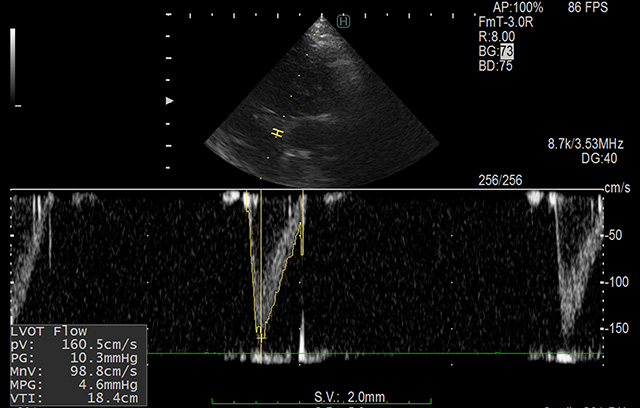

心臓エコー検査は比較的難しい検査とされています。

ですので現在は血液検査で心臓バイオマーカーを調べ心臓の状態を評価するやり方も多く行われていますが、正確な診断や心臓の状況を把握する上では心臓エコー検査は必要な検査です。当院では、心臓エコー検査をきちんと行えるエコー技術と高性能のエコー検査機器があります。